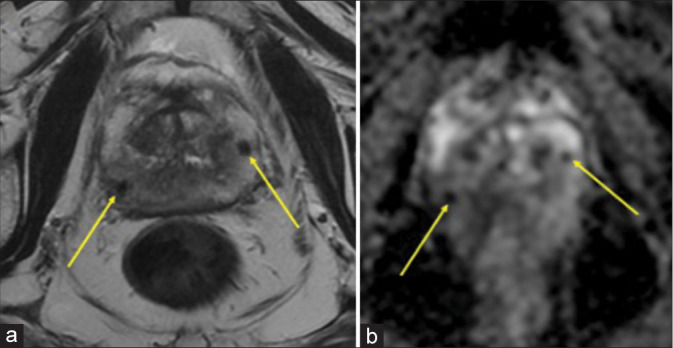

Idiopathic granulomatous mastitis is a rare, chronic inflammatory disease of the breast of uncertain etiology that can mimic breast cancer. In rare instances, it may emerge secondary to trauma to the breast. We present a case of a 66-year-old woman who initially underwent a benign stereotactic core-needle biopsy of her left breast complicated by a small hematoma which initially remained unchanged mammographically and sonographically for 1 year; then, it enlarged unexpectedly at the 21-month interval follow-up prompting an ultrasound-guided biopsy revealing granulomatous mastitis.

Abstract Image